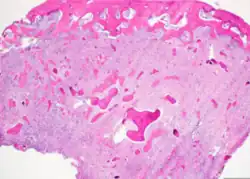

Histopathology

Cemento-ossifying fibroma is a well-demarcated lesion, often encapsulated by a thin fibrous capsule and sharply separated from adjacent normal bone. It shows significant internal variation, with differing amounts of fibrous and mineralized tissue—even within the same lesion. Mineralization is often more prominent centrally and typically includes osteoid, woven to lamellar bone, and dense basophilic cementum-like calcifications. Bony trabeculae may fuse into broad sheets or form thick, anastomosing strands. Osteoblastic rimming is commonly seen around bone trabeculae.[27]

The stroma is fibroblastic and may exhibit areas of hypercellularity and nuclear hyperchromasia; however, mitotic activity is rare and cellular atypia is minimal .[28] The mineralized component may include acellular or paucicellular cementum-like spheres along with bone structures .[28]

Though rare, hemorrhagic cystic degeneration—resembling aneurysmal bone cyst formation—can occur, more commonly in juvenile variants.[27][29] Histological overlap can exist among subtypes: psammomatoid and trabecular JOF may exhibit features resembling COF, and vice versa. In syndromic cases, such as gnathodiaphyseal dysplasia, COF lesions appear more fibrous with basophilic, acellular bone droplets and spherical ossicles, but histologically resemble nonsyndromic counterparts .[30]